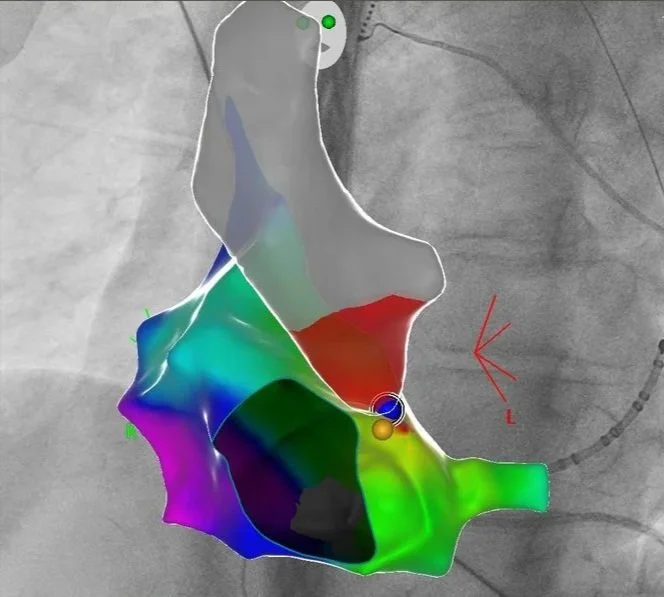

Vorhofflimmer Therapie - persönlich und individualisiert

Vorhofflimmern ist mit Abstand die häufigste Rhythmusstörung - jeder 3. Europäer wird im Laufe seines Lebens daran erkranken. Erfahren Sie mehr, wie wir Vorhofflimmern mit modernster Kathetertechnik behandeln - egal, ob Sie seit kurzem erkrankt sind, oder die Erkrankung bereits chronifiziert ist. Wir finden für Sie die richtige Technologie!

Links: Ultraschallbild eines Herzens, rechts: farbcodierte Substratkarte des Herzens